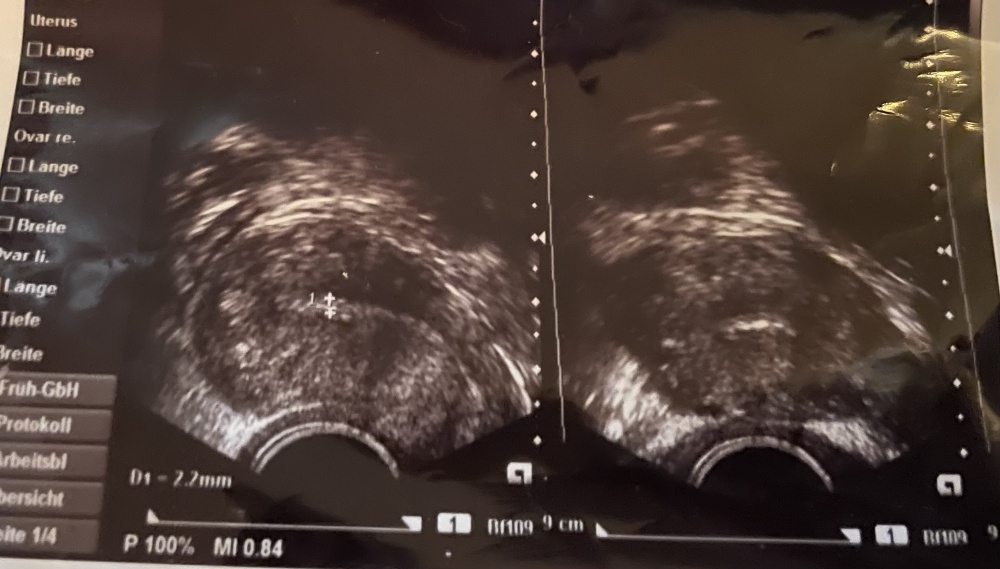

Hallo. Ich war gestern beim FA, da ich seit Tagen das Gefühl verspüre, ich hätte was im Bauch. Test war negativ, dennoch bin zum FA gegangen. Da meine im Urlaub war, bin ich zur Privatärztin, die mir dieses Bild mitgab, um es meiner FA zu zeigen.

Ich muss dazu sagen, dass wenn eine Schwangerschaft bestanden hätte, ich bereits 9+ sein müsste.. Ich war noch nie schwanger und weiß deswegen nicht, ob sich vielleicht bei dem Ultraschallbild was verstecken könnte.

sieht absolut unschwanger aus. Wenn du 9+ wärst würdest du bereits einen Fötus sehen der aussieht wie ein Gummibärchen mit Armen, Beinen Kopf und schon alles da, inklusive Herzschlag. Da wäre es kein verstecktes Punkterl.

• Für mich sieht das auch nicht nach einer SS aus. Wenn du zB bei ES+9 wärst, dann kann ein Test daheim durchaus noch negativ sein, aber in der Praxis wäre dann normal auch noch einer gemacht worden. Ob man bei ES+9 schon eine Fruchthöhle sehen sollte, weiss ich grad nicht. Bei NMT+9 sollte man aber auf jeden Fall schon eine Fruchthöhle sehen. Wenn du mit 9+ aber schon die 10. Woche meinen solltest, dann ists so wie Klumpenstein schon schrieb, da wäre definitiv schon ein gut sichtbarer Embryo da.

Zum US Bild meinte sie nur, dass sie da nichts sieht. Mir es aber trotzdem mitgibt, um es meiner Frauenärztin zu zeigen, weil ich bei einer anderen war und meine im Urlaub

• Test negativ und Ärztin sieht nichts am US, dann sollte es die 10. Woche sein…

Da wird wohl ziemlich sicher nichts sein.